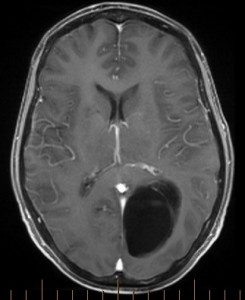

Arachnoid cysts such as the one shown above can sometimes present with progressive neurological dysfunction. This patient’s cyst gradually enlarged and she was referred when her vision contiunued to deteriorate. The pre-operative images (upper three images) show a sizeable cyst causing mass effect on the patient’s “visual pathway” fibers (geniculo-calcarine tract; tractography lower left).

The cyst was successfully fenestrated (openings made into the cyst’s walls and its internal septations, allowing better fluid passage and drainage) at multiple locations through a small precisely-made stereotactic craniotomy (lower middle and lower right images), and the patient’s long-standing vision problems then substantially improved. The image below shows the commencement of microsurgical fenestration (yellow circle) of an arachnoid cyst wall (ACW) for this enlarging and symptomatic cyst located along the brainstem (B-S). The tip of the microinstrument shown here is 5mm in diameter.